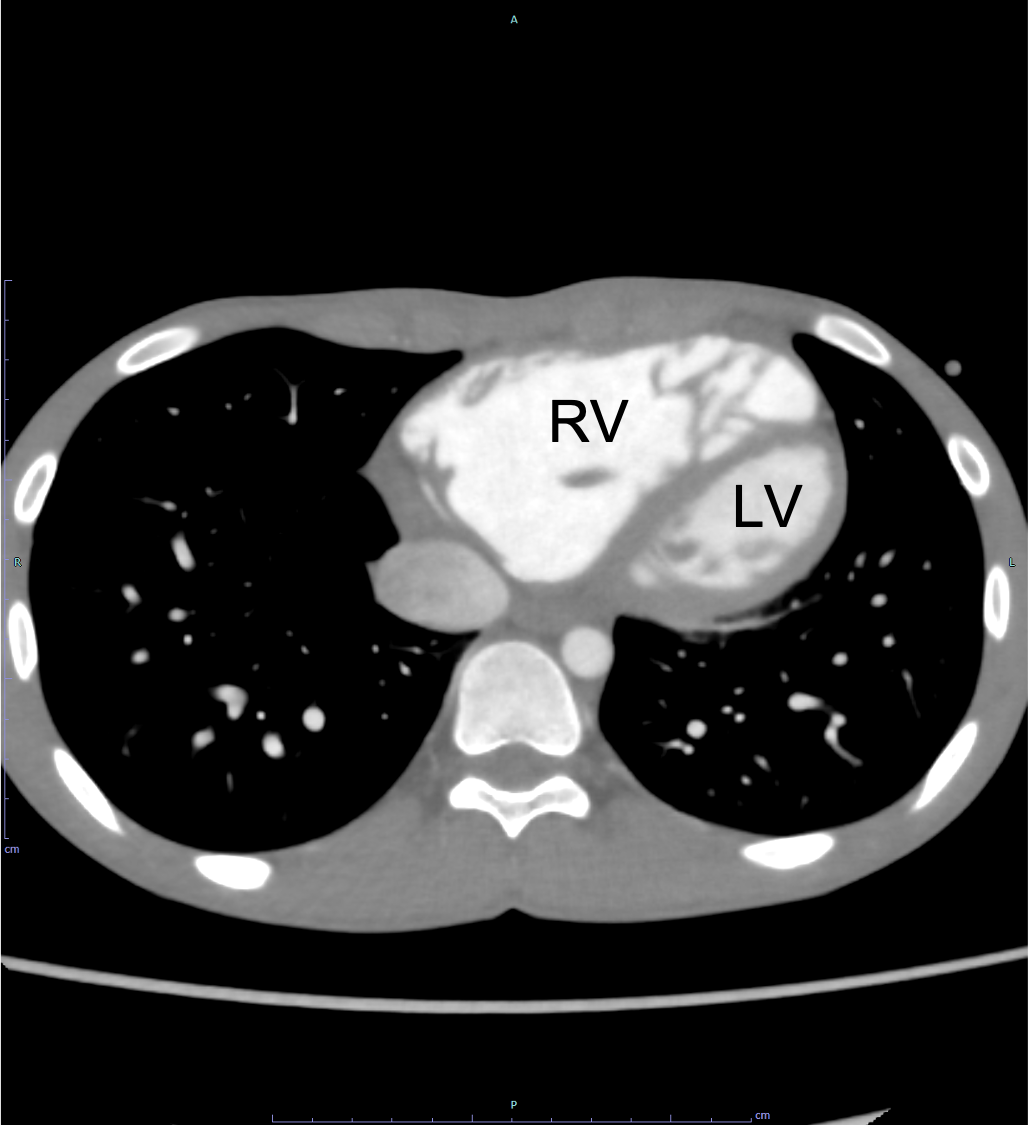

図5.心電図同期造影CT水平断(動脈相、外科的修復術後)

欠損孔は閉鎖されている。(矢印)右室の拡大にも改善を認める。